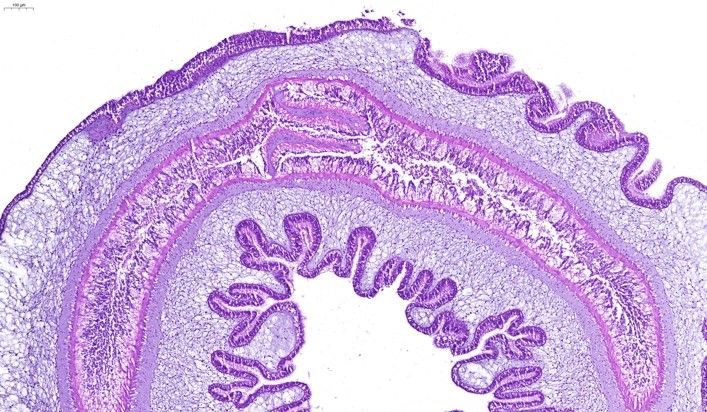

海腎腸道HE染色

HE染色

262